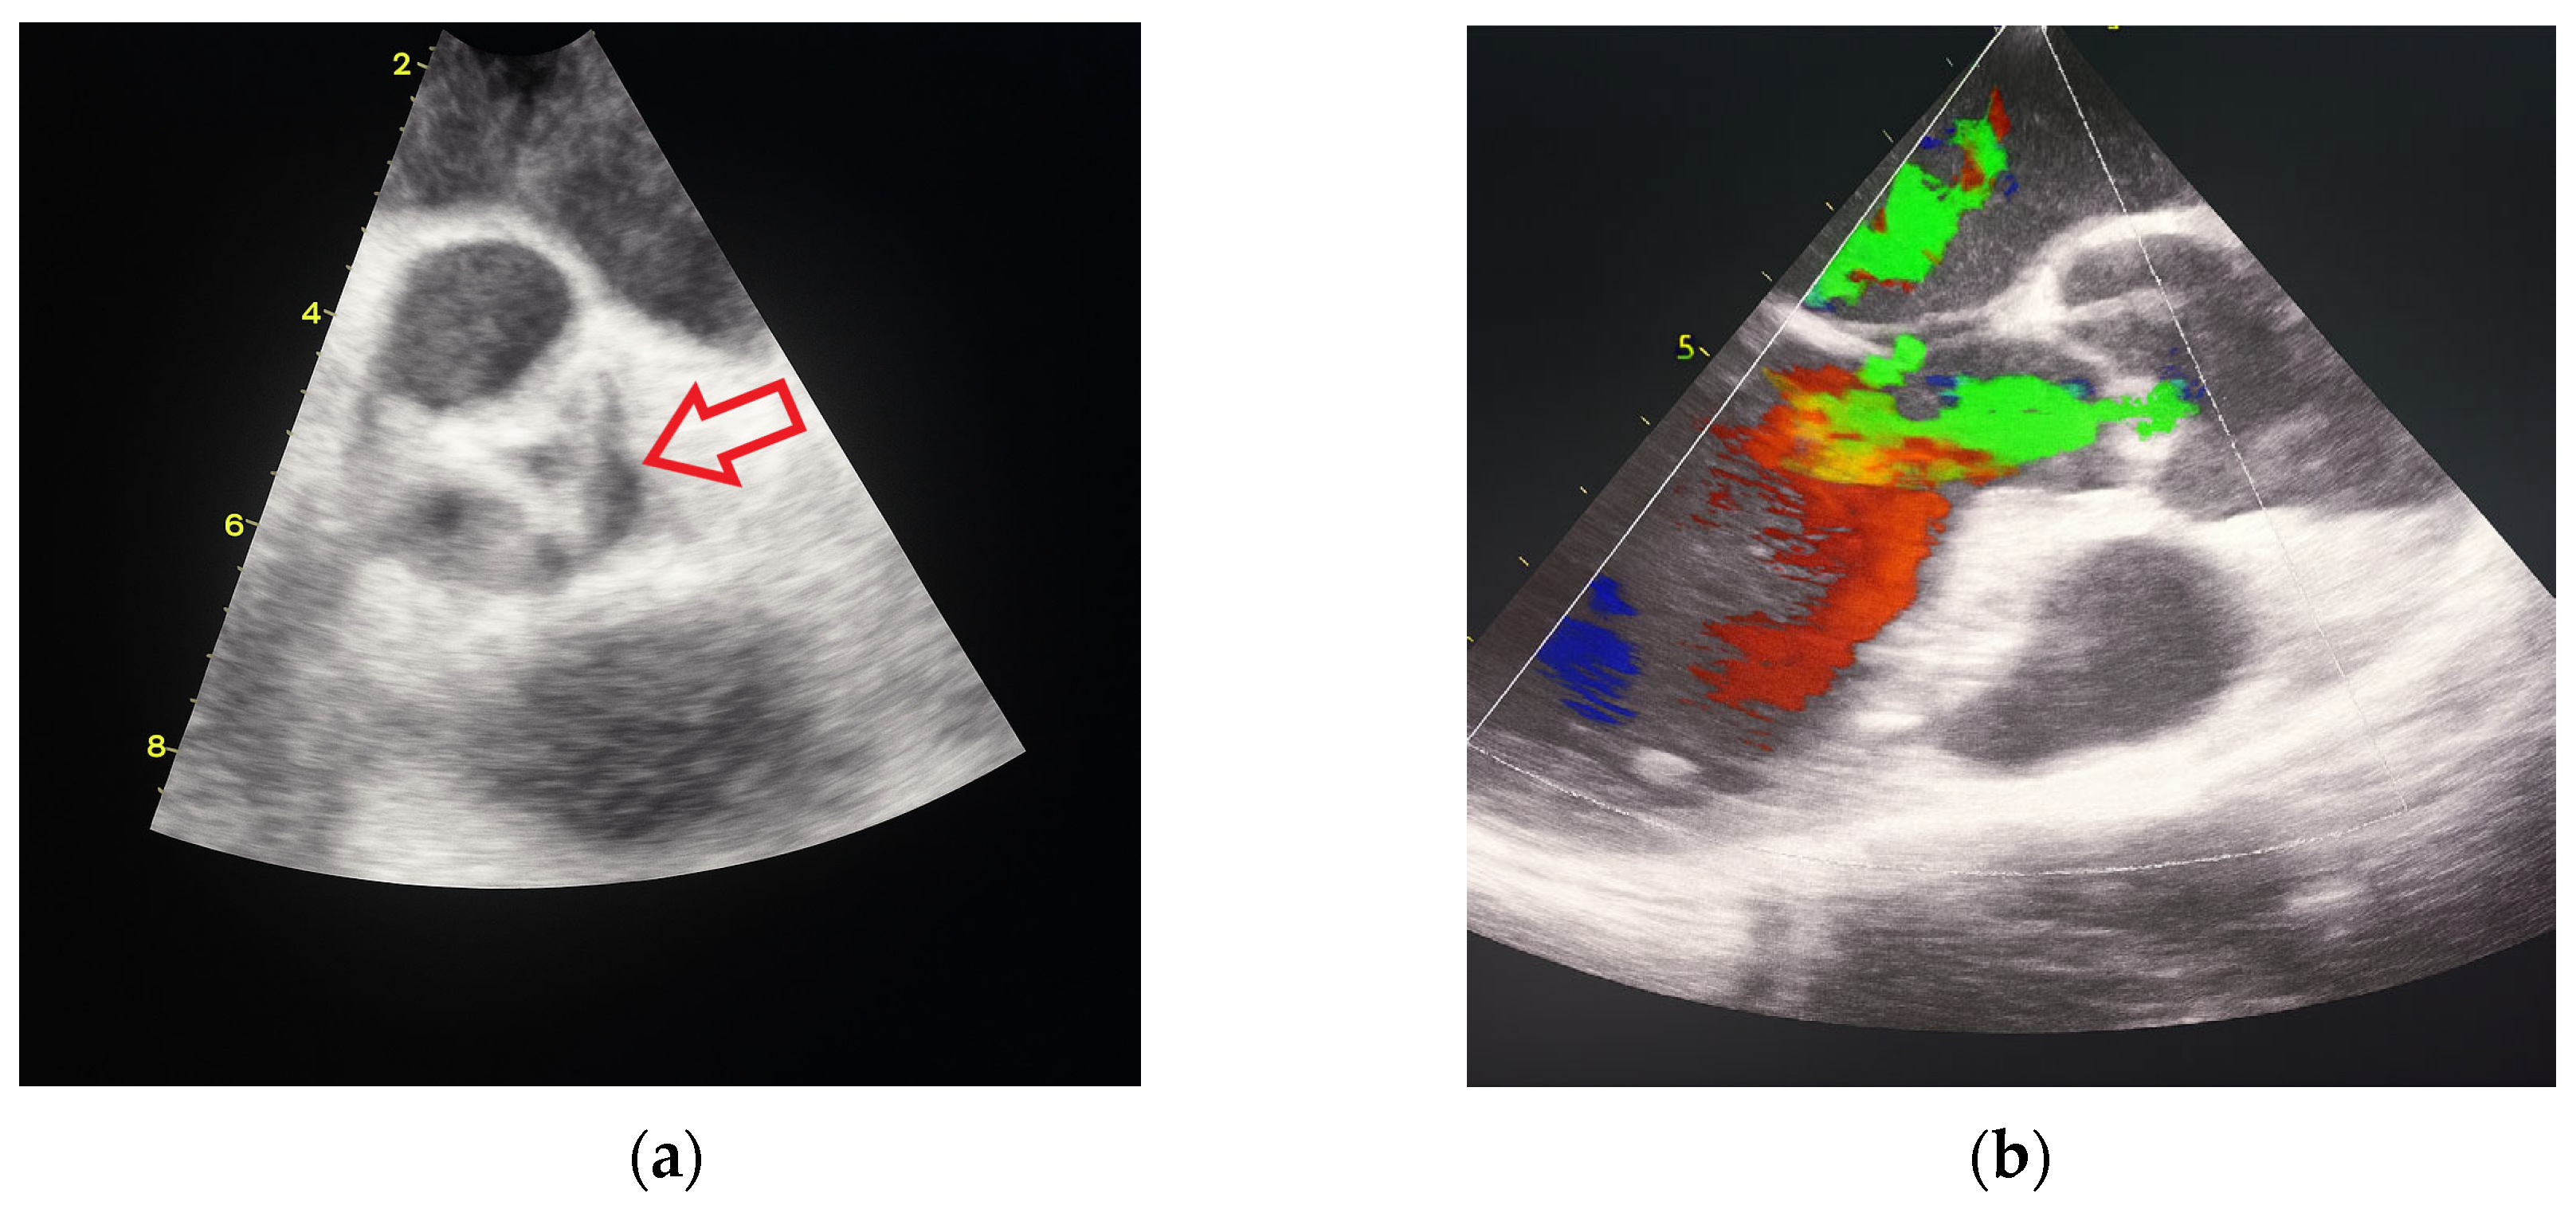

In October 2024, the patient was admitted to our Division of Rheumatology and Immunology due to exacerbation of her underlying overlap syndrome, demonstrating moderate to high disease activity: Disease Activity Score 28-ESR was 4.95 and Systemic Lupus Erythematosus Disease Activity Index was 6. Clinical symptoms included continuous moderate chest discomfort and worsening dyspnea upon exertion. She denied gastrointestinal or respiratory complaints, fever, or systemic signs of infection. Her long-term pharmacotherapy regimen included prednisone 7.5 mg/day, pantoprazole 40 mg/day, atorvastatin 20 mg/day, cholecalciferol 20,000 IU weekly, furosemide 40 mg/day, and lercanidipine 10 mg/day. Vital signs on admission were stable: blood pressure 140/90 mmHg, heart rate 76 bpm, and temperature 36.7 °C. Cardiovascular auscultation revealed a grade 2/6 systolic murmur over the precordium. Musculoskeletal examination was notable for bilateral wrist synovitis, bilateral shoulder pain with restricted range of motion, right knee arthralgia with limited mobility, and fixed flexion deformities of the right-hand fingers and left elbow. There was no clinical evidence of peripheral edema. Laboratory evaluation revealed: leukocytes 6500/µL, hemoglobin 88 g/L, platelets 188,000/µL, C-reactive protein (CRP) 11.7 mg/dL, erythrocyte sedimentation rate (ESR) 50 mm/h, hypocomplementemia (low C3 and C4), serum urea 4.9 mmol/L, and serum creatinine 144 µmol/L. Immunological testing showed negative RF and ACPA. Antinuclear antibodies (ANA) were positive at a titer of 1:160 with a homogeneous nuclear staining (AC-1 pattern). Anti-dsDNA was markedly elevated (86 IU/mL), and antiphospholipid antibodies (aPL), including lupus anticoagulant (LA), were triple positive. All other extractable nuclear antigens tested negative. High-sensitivity troponin I was elevated (84.0 ng/L), whereas N-terminal pro b-type natriuretic peptide (NT-proBNP) remained within normal limits (68.5 ng/L), and ECG findings were unremarkable. Due to persistent anemia, dyspnea, and dysphagia, repeat esophagogastroduodenoscopy was performed, confirming histologically proven erosive Helicobater pylori-negative gastritis. Repeat MSCT coronary angiography again ruled out acute coronary syndromes. Repeat TTE revealed a degenerative bicuspid aortic valve with a rudimentary left coronary cusp and moderate AR (aortic valve area: 2.4 cm2; vena contracta: 4 mm). Transesophageal echocardiography (TEE) confirmed these findings and offered a more detailed evaluation of valvular morphology and the severity of AR (Figure 2 and Figure 3).

Figure 2.

Transesophageal heart ultrasound 2D imaging: (a) degeneratively changed bicuspid aortic valve with rudimentary left coronary cusp (red arrow). (b) 2D visualization of moderate aortic regurgitation in the context of a pathologically altered aortic valve.